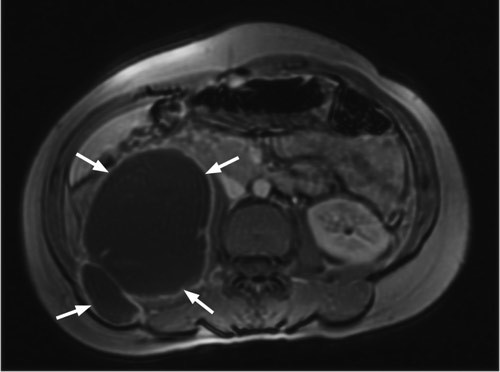

Hun hadde en senkningsreaksjon på 49 mm/t. Andre orienterende blodprøver, inkludert hivtest, var normale. Røntgen thorax og urindyrking for mykobakterier var negative. MR abdomen viste funn som ved spondylodiskitt i nivå Th11/Th12 med en stor senkningsabscess i høyre m. psoas (til venstre). Abscessen målte ca. 14 cm kraniokaudalt og strakte seg kaudalt i høyde med virvelcorpus L5. Til høyre ses et tverrsnitt av abscessen. Mikroskopi av abscessmaterialet viste ingen funn av syrefaste staver. Dyrking og polymerasekjedereaksjon (PCR) viste funn av Mycobacterium tuberkulosis. Det ble drenert ca. 350 ml puss og startet med langvarig tuberkulostatikabehandling. Kvinnen følges regelmessig med polikliniske kontroller.